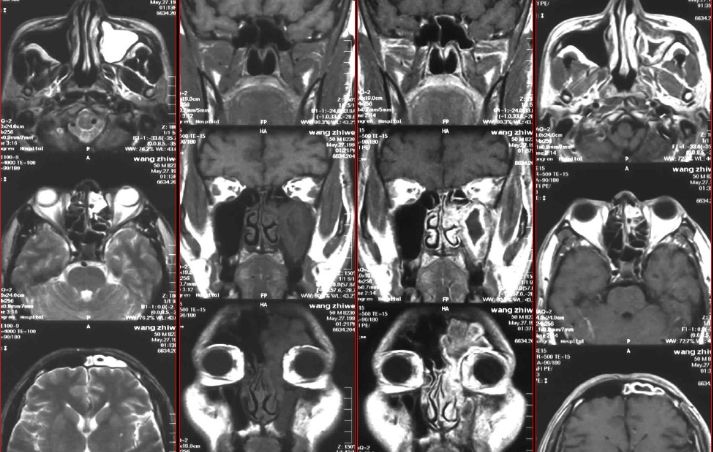

鼻窦炎—骨质改变

鼻窦炎—骨质增生

鼻窦炎—骨质增生及脑膜炎